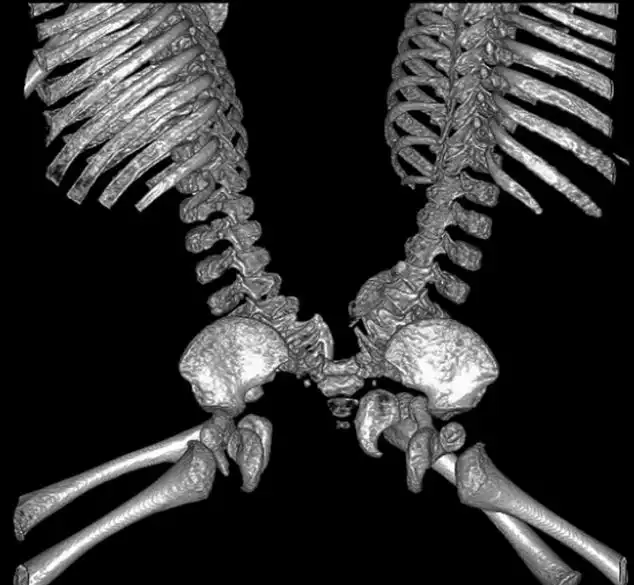

Темнокожие мальчики Иисус и Иаков родились на свет соединенными спина к спине в области таза и нижней части позвоночника. Часть желудочно -кишечного тракта у них тоже была общей. В остальном же они были полностью функциональны и здоровы.